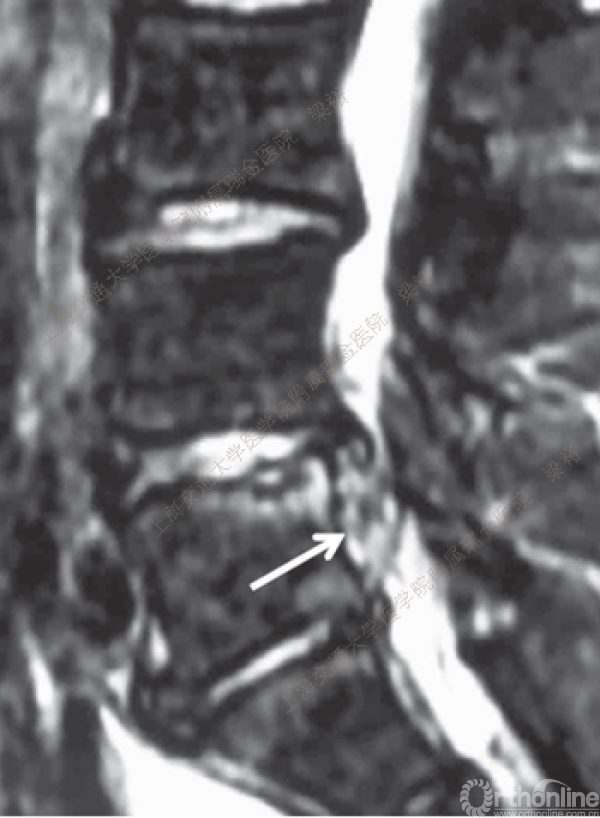

随着微创技术的发展以及手术经验的积累,脊柱微创手术已开始逐步取代传统的脊柱外科手术。微创手术已涉及从颈椎到腰椎的整个脊柱。从简单的椎间盘手术到复杂的 脊椎手术,手术类型越来越多样。在所有的脊柱微创手术中,尤其脊柱内镜手术在过去10年中取得了惊人的进步。在技术发展的同时,脊柱内镜的手术并发症问题也逐渐浮出了水面,针对脊柱内镜手术的并发症与其对策,上海交通大学医学院附属瑞金医院梁裕教授介绍了他们的经验。